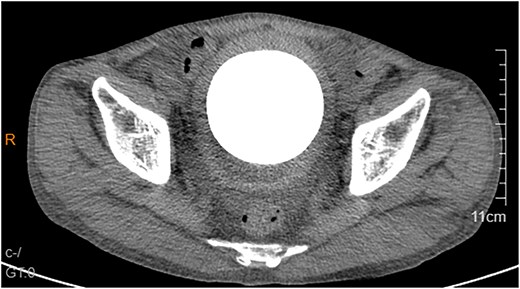

A 53-year-old male, presented to a local hospital in April 2021 due to lower back discomfort. There was no weight loss, fatigue, fever, or other systemic symptoms. Urinalysis showed leukocytes (+++); computed tomography (CT) revealed a 76 × 74 mm stone, bladder wall thickening, and dilation of the bilateral renal pelvis and ureters (Fig. 1). Subsequently, he underwent pubic bladder incision for stone removal and bladder diversion at that hospital. Postoperatively, the incision site was swollen, exuding fluid, and did not heal over an extended period. A total of 14 months after the initial surgery, he was admitted to our hospital. On examination, there was excessive granulation tissue proliferation around the bladder incision wound and near the bladder diversion tube, with surface exudation and easy bleeding upon touch (Fig. 2). Upon admission, urinalysis showed leukocytes (++), occult blood (++), glucose (++), and protein (++). Postprandial blood glucose level was 19.58 mmol/l. Urine culture indicated tropical pseudo-filamentous yeast and Enterococcus. Secretion culture showed E. coli and Klebsiella pneumoniae subsp. Blood routine test indicated white blood cell count and highly sensitive C-reactive protein within normal ranges. He received infection control, glucose management, and wound care, but the wound did not heal. Abdominal CT and pelvic magnetic resonance imaging (MRI) revealed bladder wall thickening and soft tissue in the anterior pelvic area (Fig. 3). Histopathological results from abdominal wall tissue biopsy indicated moderately differentiated squamous cell carcinoma. Immunohistochemistry indicated: CK(pan)(+), CK20(−), CK7(−), PAX-8(−), GATA3(−), P63(+), P53(+), Ki-67(+) at 40% (Fig. 4).

Abdominal CT and pelvic MRI revealed bladder wall thickening and soft tissue in the anterior pelvic area.